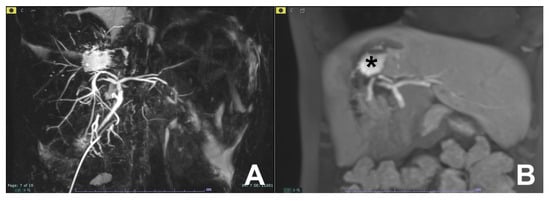

| Biliary leak after surgery or trauma | HASTE T2 | AXIAL | -- | -- | Anatomy and liquids analysis |

| INDICATIONS: MRI, thanks to the use of liver-specific MR contrast agents, can easily detect the site of bile leak. | HASTE T2 | CORONAL | -- | -- | Anatomy and liquids analysis |

| MRCP 3D | OBLIQUE CORONAL | -- | -- | Biliary anatomy and calculi | |

| GRE T1 IN/OUT | AXIAL | -- | -- | Steatosis | |

| GRE T1 3D DYNAMIC | AXIAL | Not necessary | YES high resolution | Useful for leak | |